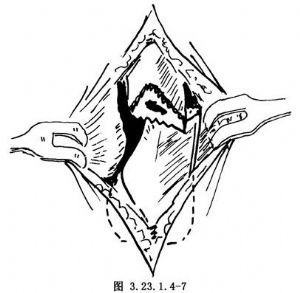

1.切口 以跖骨骨折部为中心,做一长3~4cm背侧纵切口(图3.23.1.4-6)。沿皮肤切口线切开深筋膜和骨膜,做骨膜下剥离,显露出跖骨骨折的近侧段和远侧段(图3.23.1.4-7)。